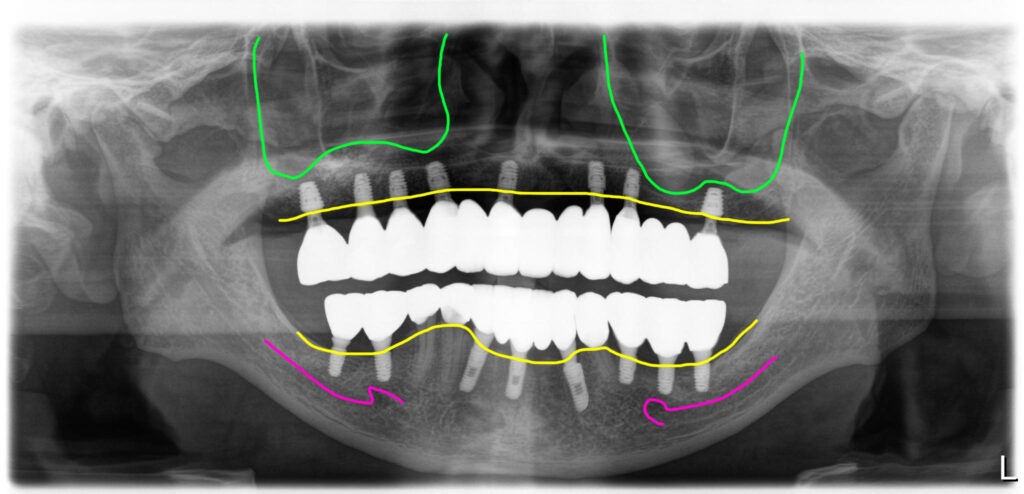

상악 8개, 하악 8개로 전체치아를 완성

수술 후 6개월을 기다렸습니다. 그 이유는 상악동 윈도우 뼈이식한 부위 때문입니다. 상악동 윈도우 뼈이식을 한 경우에는 기본 6개월 후에 다음 치료가 이루어지는 것이 통상적입니다.

그래서 수술 후 6개월째에 스캔을 한 다음 최종보철을 지르코니아로 완성했습니다.

뼈가 많이 부족했지만 수술을 한 번에 진행했고 내원횟수 4번에 치료를 마무리했습니다. 건강해서 남긴 자연치는 다시 크라운을 씌워 주었구요.